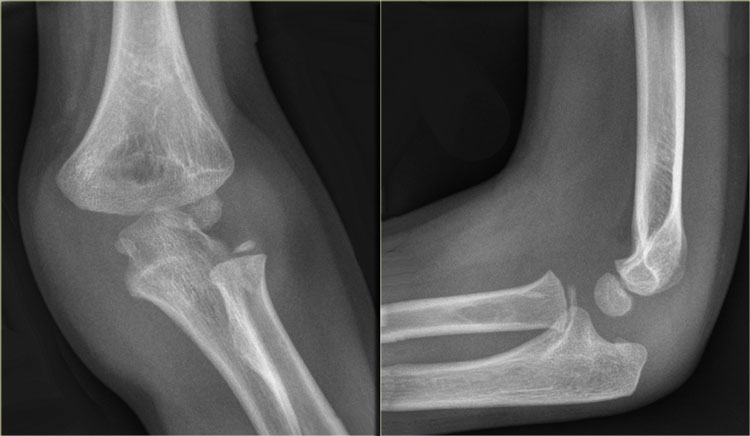

The order of appearance of the ossification centres is specified in the mnemonic C-R-I-T-O-E. The order of appearance of the ossification centres is specified in the mnemonic C-R-I-T-O-E.

Ossification centres

There are 6 ossification centres around the elbow joint.

They appear and fuse to the adjacent bones at different ages.

It is important to know the sequence of appearance since the ossification centers always appear in a strict order.

This order of appearance is specified in the mnemonic C-R-I-T-O-E (Capitellum - Radius - Internal or medial epicondyle - Trochlea - Olecranon - External or lateral epicondyle).

The ages at which these ossification centres appear are highly variable and differ between individuals.

It is not important to know these ages, but as a general guide you could remember 1-3-5-7-9-11 years.